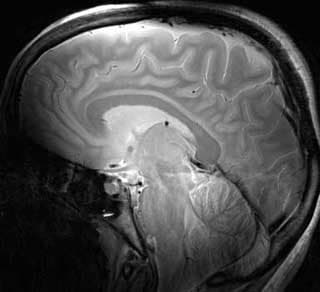

- CourseFreeFunctional Magnetic Resonance Imaging: Data Acquisition and AnalysisStarts: AnytimeFormat: Online

- CourseFreeMagnetic Resonance Analytic, Biochemical, and Imaging TechniquesStarts: AnytimeFormat: Online